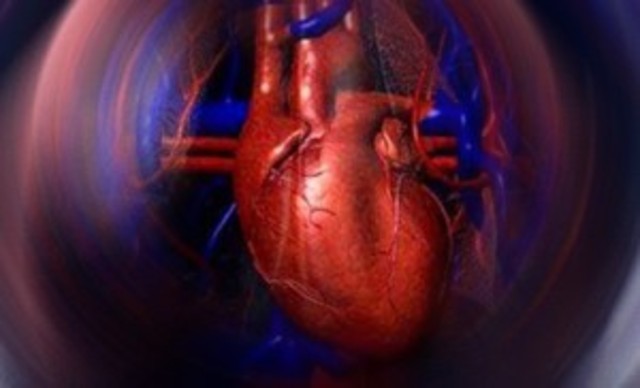

• Biomaterial - Protesis valvular cardíaca

Biomaterial - Protesis valvular cardíaca

Realizada por primera vez en St Jude en 1977. La protesis valvular cardiaca son valvulas del corazón fabricadas o preparadas industrailmente que ayuda a que los pacientes con insuficiencias carciacas en alguna de las 4 valvulas puedan llevar una vida normal y saludable. Los materiales de los que puede estar fabricada una valvula son: Carbón pirolítico, Ti, PFTE, silicona o tejido reprocesado.